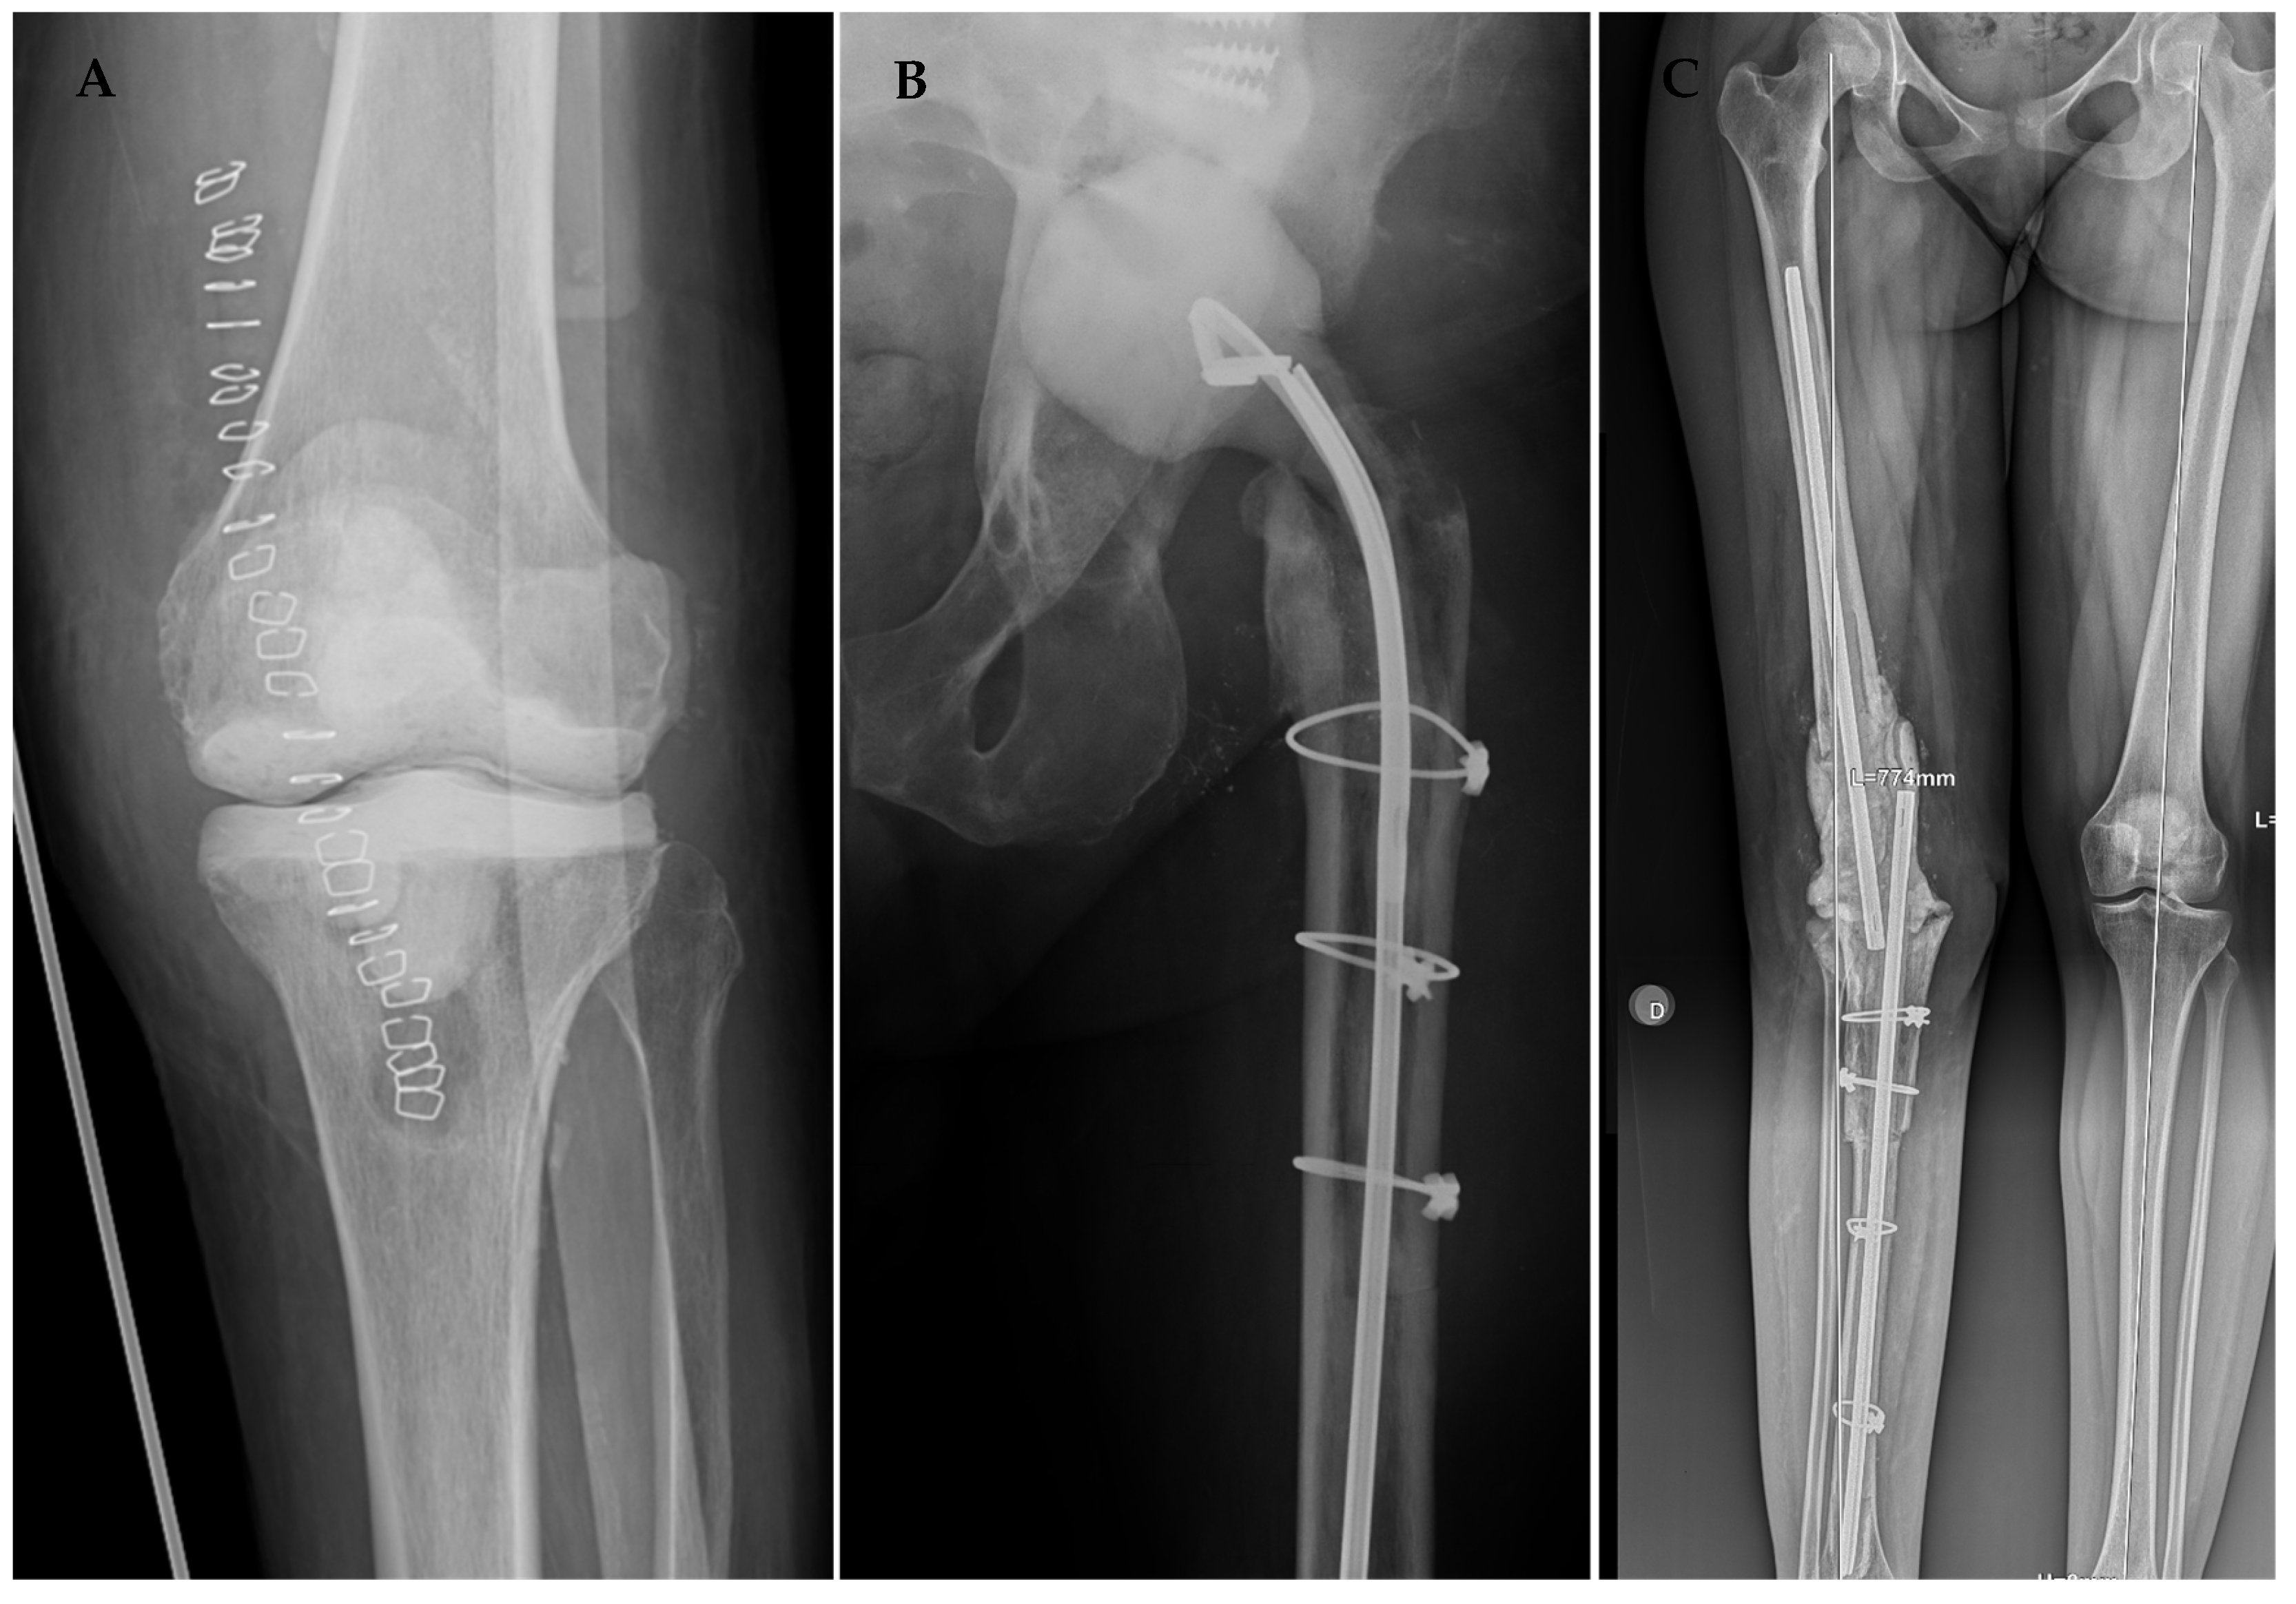

Figure 4. Radiological outcomes of our surgical protocol after the first stage of a knee articulated spacer (A), hip articulated spacer (B), and static knee spacer (C) secondary to an extensive bone defect.

The knee-articulated cement spacer was molded by hand if minor bone defects were present (Figure 4A). For patients with significant bone defects or lacking collateral ligament support, we utilized a relatively constrained ball-and-socket spacer, following the technique described by MacAvoy and Ries. In this technique, a convex femoral spacer is shaped using the bulb portion of a rubber irrigation syringe as a mold. The tibial spacer is formed by placing cement in the doughy phase on the proximal tibia and using the bulb washing syringe to create a hemispherical concavity. Any additional cement is used to fill bony defects, which are addressed when placing the spacer.

In hip revisions (Figure 4B), the femoral head was also fashioned using the mold of a washing syringe, inverted to utilize the smooth part on the cephalic screw or Kuntscher´s nail, as we have described in previous publications [21]. After confirming adequate acetabular congruency, the nail was coated with cement, with attention paid to avoiding excessive material in the trochanteric zone to prevent complications during closure. Small perforations were made in the cement layer at the trochanteric level for subsequent reattachment of the abductor and psoas muscles. Finally, the nail was entirely coated with cement and placed intramedullarily.